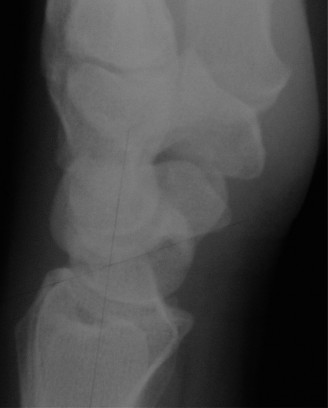

Identify neurovascular complications of perilunate injury? CASE 4 ### A patient presents with deep-seated pain in the mid-dorsal aspect of the wrist. There is no history of trauma. Examination is inconclusive except for some tenderness over the dorsal aspect of the scapholunate joint. X-ray (Fig. 3–6) is as follows. What is your diagnosis?

Figure 3–6(©) Sunil Thirkannad and Christine M. Kleinert.

The correct answer is (E). The x-ray shows a sclerotic lunate which should raise the suspicion of Kienbock’s disease.

What radiological finding is commonly known to be associated with Kienbock’s?

The correct answer is (D). An ulna-negative variance, wherein the distal end of the ulna is shorter than the distal end of the sigmoid notch of the radius, is known to be associated with Kienbock’s disease. While the exact cause–effect relation between the two has not been established with certainty, it is hypothesized that a shorter ulna leads to increased loading at the radiolunate joint, predisposing the lunate to avascular necrosis.